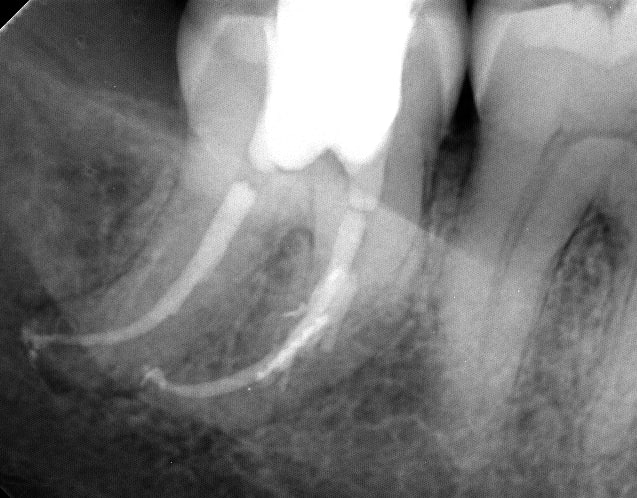

Endo de ce matin :

--

Je remets celles que j'ai faites hier on sait jamais si quelqu'un est intéressé (mais je venais sur ce post surtout pour avis dans la démarche.

Je pense me faire un "book" en plus (où je mettrais tout, réussi comme raté.)

Toutes mes endos d'hier (elles sont dans un autre sujet aussi)

Tu obtures à quoi pour avoir autant de puffs? Par contre ça a l’air efficace sur les canaux accessoires.

Zizine Zial pour le ciment. pas de desmodontites (très très rares). Les canaux accessoires c'est l'EDTA qu'il faut remercier, et au Mac Spadden je reste un bon moment (5-6 secondes) à 3 mm de l'apex à 30000 tours, et parfois en plus je condense verticalement jusqu'à 4-5 mm de l'apex et je remets un coup de Mac Spadden.